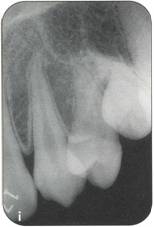

Fi 545e45f g 5-8i Radiographic evaluation of the donor tooth. Several angulations should be used to determine the likely fit of the donor tooth into the recipient site. If the first premolar is double-rooted, consider using the second premolar as a donor tooth. |

|